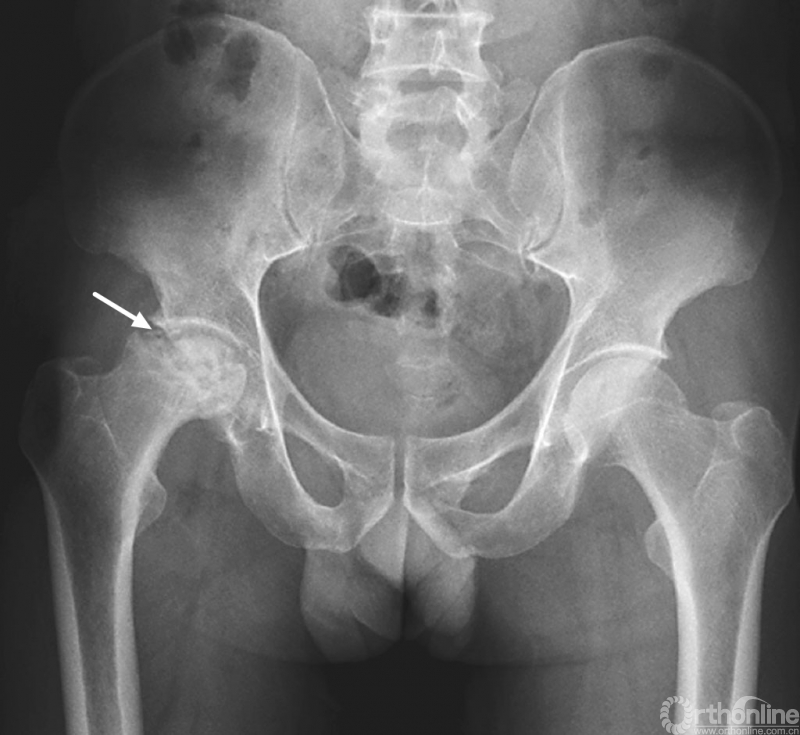

成人股骨头缺血坏死(晚期)

右股骨头塌陷加重

股骨头塌陷加重,甚至碎裂,承重区关节间隙变窄。股骨头内硬化区和透光区混合存在或伴有内外并行的透光带和硬化带。可继发退行性骨关节病、病理性骨折及半脱位,退行性骨关节病表现为股骨头及髋臼边缘增生、髋臼关节面增生硬化。